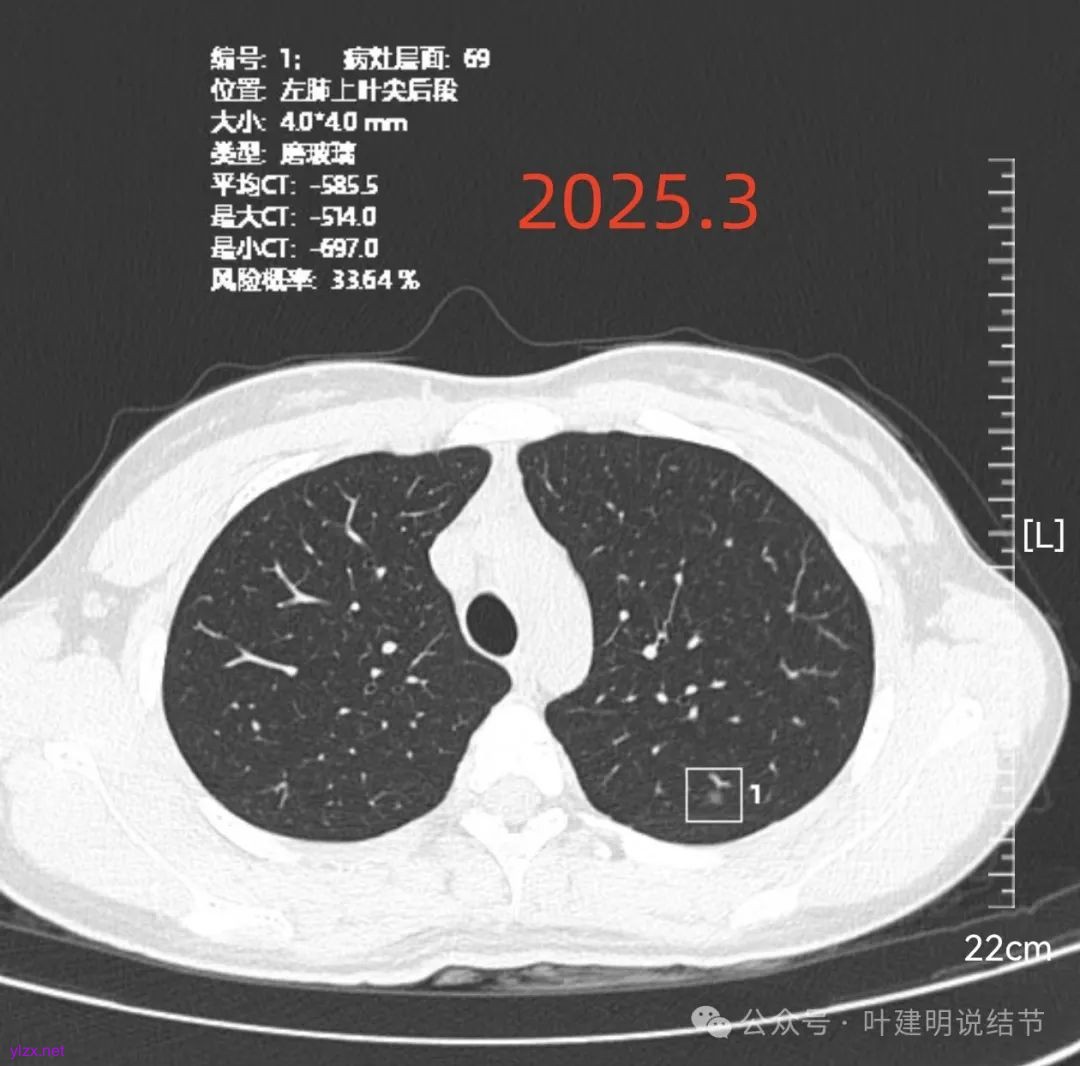

再看2025年3月的影像:

各病灶均无明显吸收好转,但显然也说不上有明显进展。所以基本上要考虑是肿瘤范畴的(包括肺泡上皮不典型增生或肺泡上皮增生)。但危险性显然不算高,至少近2年了没有什么进展,即使病灶6最厉害的也是纯磨密度伴空腔。

再来看风险最大的病灶6的连续层面:

血管从旁过,没有受结节影响。